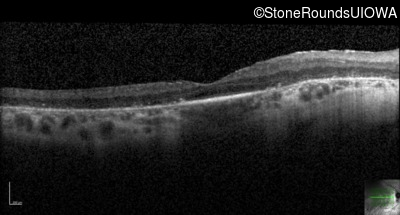

Optical Coherence Tomography - Left - 20/70

Exemplar / OCT Stack